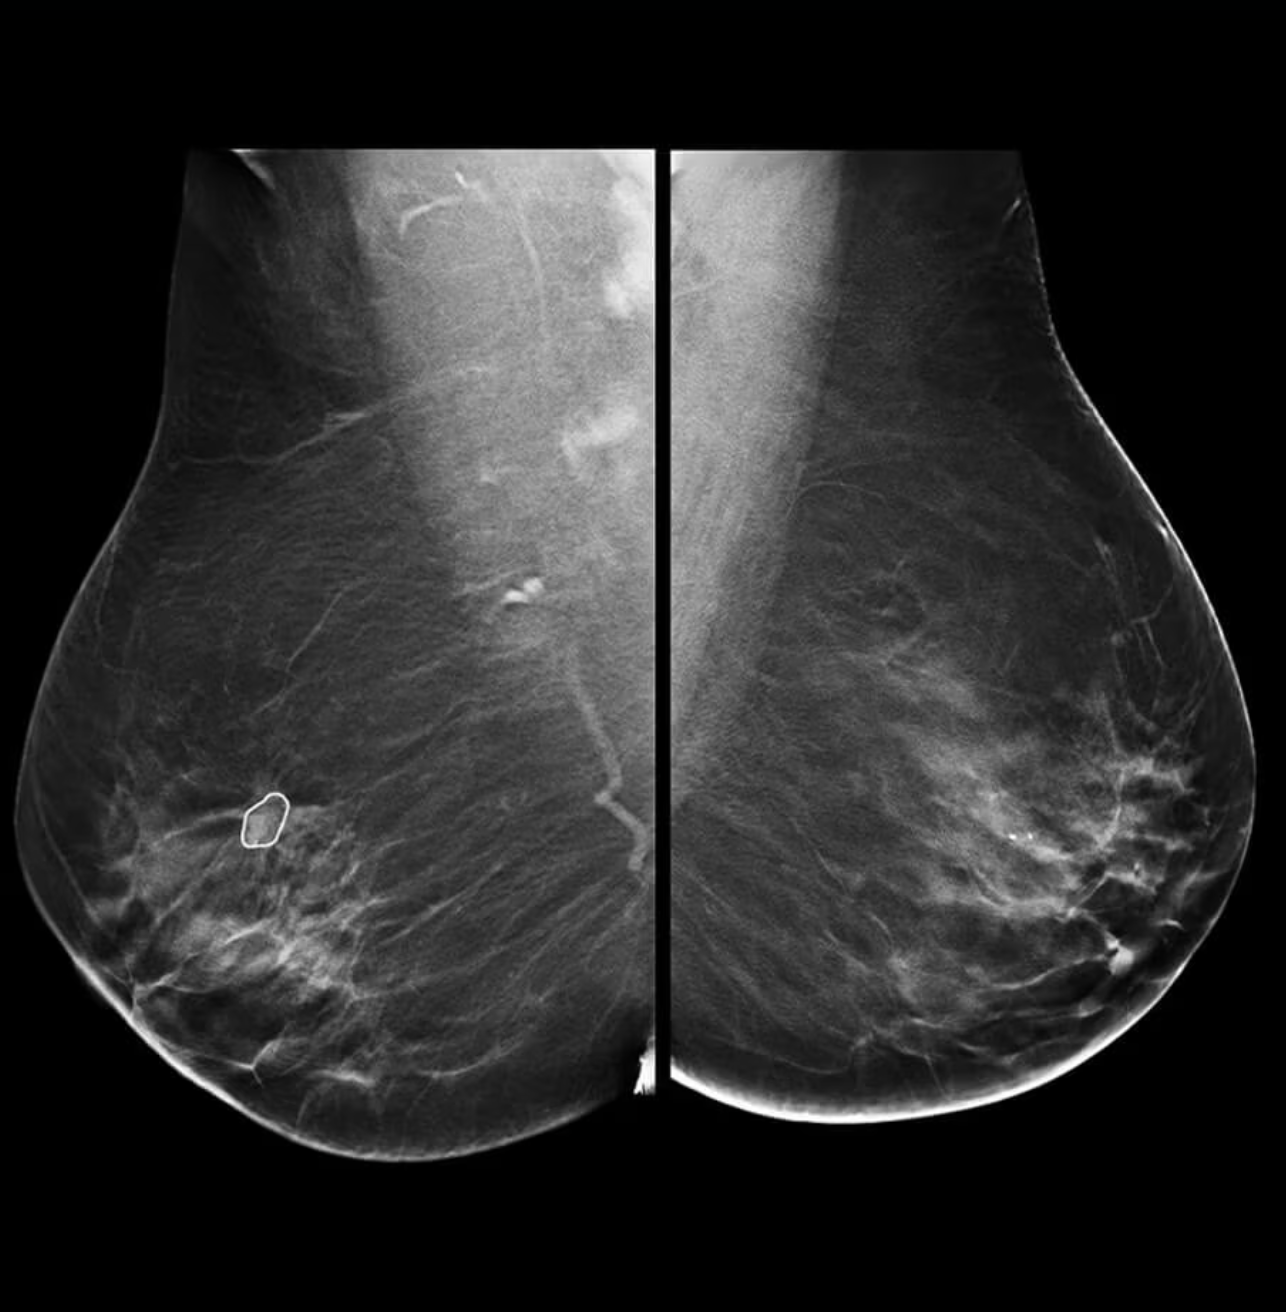

GE HealthCare’s latest MyBreastAI Suite provides an all-in-one AI platform optimized for mammography to support clinicians with breast cancer detection. With this initial release, MyBreastAI Suite integrates three AI applications from iCAD including ProFound AI for DBT, SecondLook for 2D Mammography and PowerLook Density Assessment to help support early detection and improve patient outcomes, as well as help radiology departments improve operational productivity.

With Pristina Bright, clinicians can see lesions that cannot be seen on routine mammography4 5 6 and biopsy what is seen within 15 minutes.7 To help improve overall productivity, Pristina Bright can also help providers take more patients on their system, with the ability to image up to 30 patients a day with contrast mammography8 through an easy-to-read exam.

“Through our research and clinical experiences, contrast enhanced mammography (CEM) continues to emerge as game-changer in helping to improve breast cancer outcomes for patients facing this difficult diagnosis,” shares Dr. Jordana Phillips – Radiologist at Boston Medical Center. “When it comes to findings that are difficult to define, CEM leverages the addition of a contrast agent to highlight unusual areas of blood flow – providing an efficient yet familiar, patient-centric approach to evaluate the presence of cancer with high sensitivity and specificity. With contrast, we’re able to turn a normal mammogram into something that provides so much more information which accelerates our ability to make a confident diagnosis. We’re excited to be joining GE HealthCare and the breast imaging community at SBI 2024 to share more about our experience through the hands-on learning course, as well as share how we’ve implemented CEM as part of our efforts to provide personalized breast cancer care to community we serve.”

- SenoBright HD Contrast Enhanced Mammography (CEM), which combines mammography and vascular-based screening methods to highlight areas of unusual blood-flow patterns that may indicate malignancy – helping reduce the masking effect of fibro glandular breast tissue so lesions can be more clearly identifiable; and